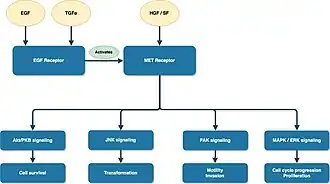

Type 1 PRCC is caused by a genetic mutation or a gain in chromosome 7 where the MET gene is positioned, resulting in the promotion of oncogenic pathways in renal epithelial cells.[6] Typically, the MET gene is upregulated for renal tissue repair and regeneration by encoding the receptor tyrosine kinase c-MET of hepatocyte growth factor.[6] However, activation of the oncogenic pathway in the MET gene will manifest invasion, anti-apoptosis, angiogenesis, and metastasis.[6]

Several medications that target molecular pathways in RCC have been possible options for advanced and metastatic PRCC.[9] Among different medications, tyrosine kinase inhibitors (TKIs) and mammalian target of rapamycin (mTOR) inhibitors are effective in inhibiting angiogenesis, blocking growth and suppressing spread of the tumor.[38] Sunitinib, sorafenib, and axitinib are TKIs with anti-vascular endothelial growth factor (VEGF), which inhibit cellular signaling by targeting multiple receptor tyrosine kinase.[38][39][40][41] Everolimus and temsirolimus are used in deregulating the mTOR pathway.[42][43] Specifically, mTOR inhibitors have crucial roles in regulating cell growth, cell proliferation and metabolism of highly active tumor cells.[38] Other targeted agents such as MET inhibitors, epidermal growth factor receptor (EGFR) inhibitors, and monoclonal antibodies, are also promising treatment approaches for PRCC.[9] Foretinib is one example of a multikinase inhibitor targeting c-MET.[44] Considering that MET gene mutation is one oncogenic pathway of PRCC, MET inhibitors like tivantinib and volitinib are currently being investigated as a new targeted therapy option.[9][44]